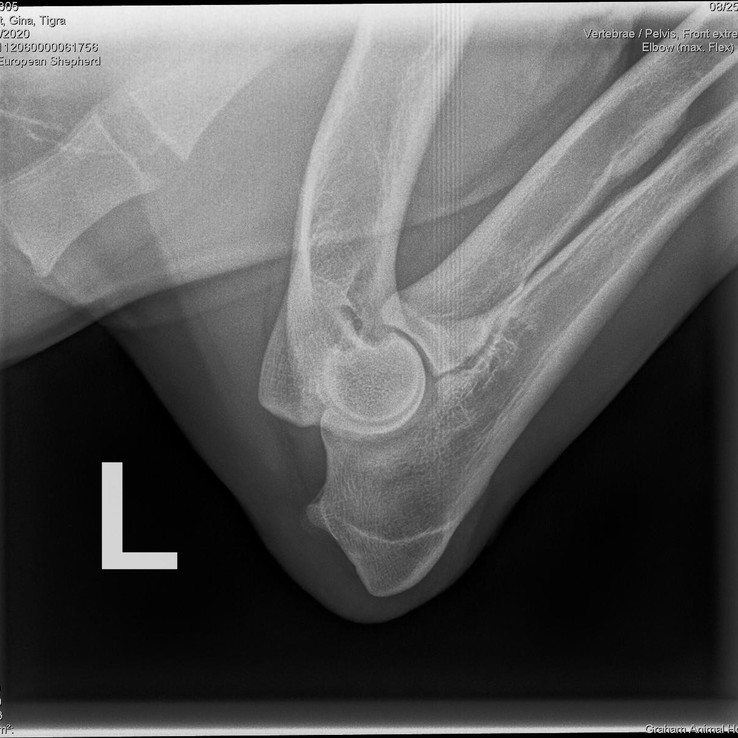

Tigra

Date of Birth: July 10, 2020

Weight: 91 lbs (41 kg)